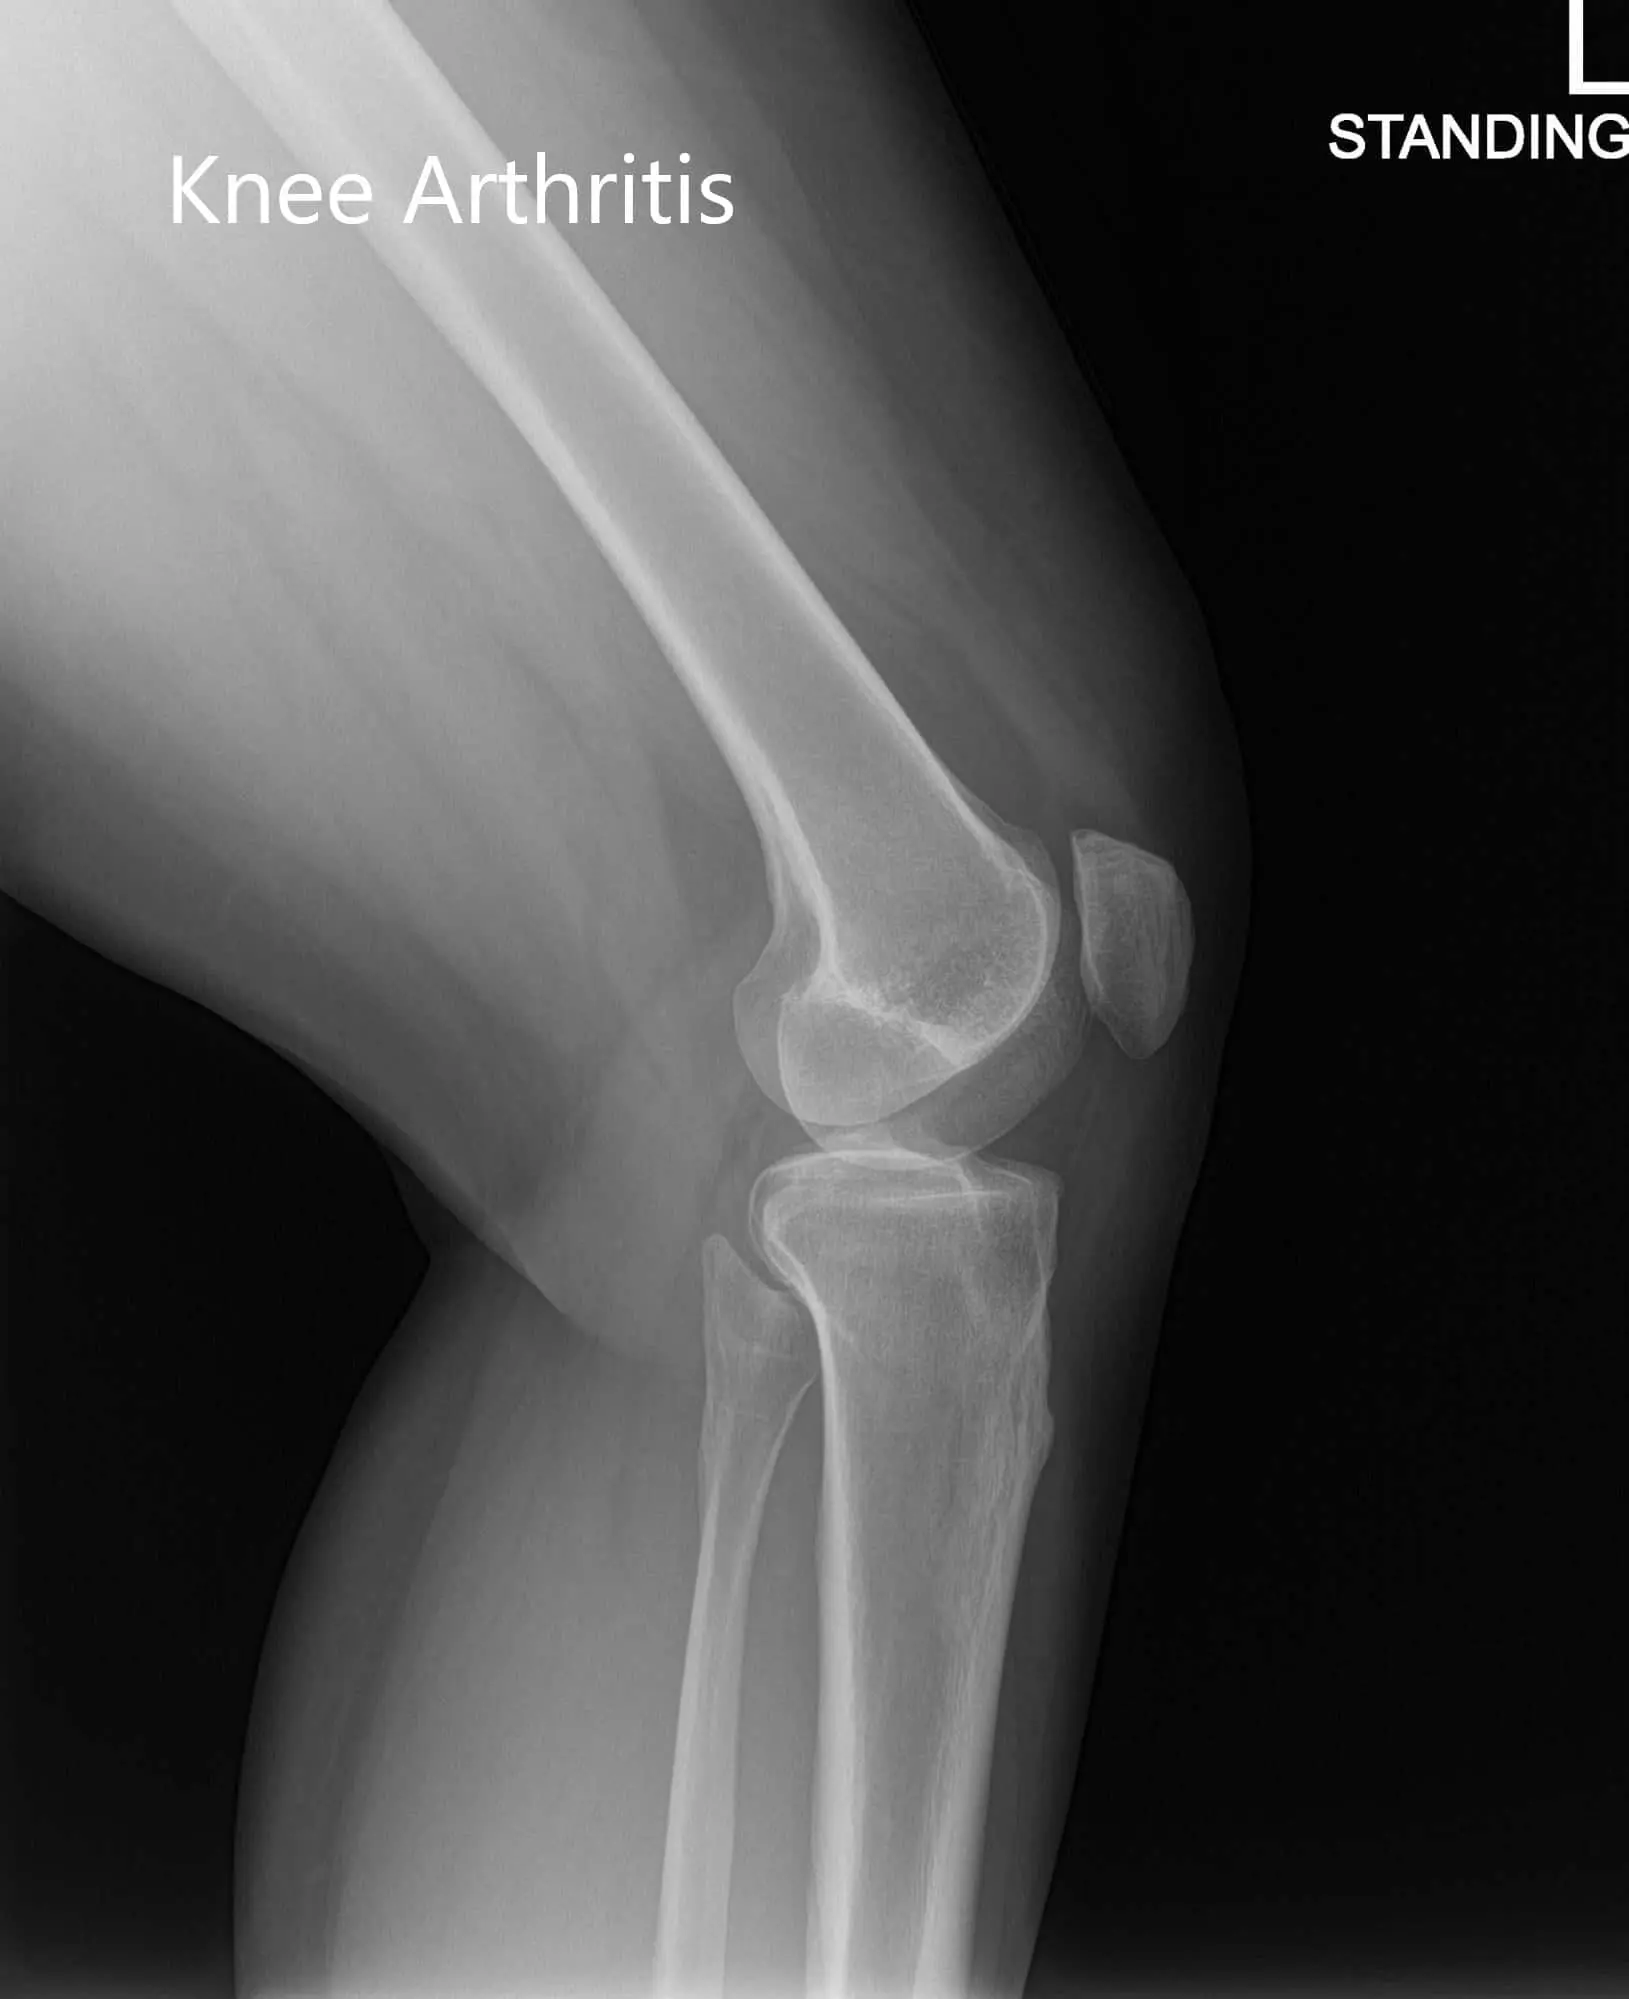

His physical examination revealed tenderness of the medial joint line with mild swelling. The knee revealed no instability on anterior, posterior, valgus and varus stress tests. Imaging revealed post-traumatic arthritis of the left knee. He was given a cortisone knee injection with excellent control of pain. Subsequently, the patient was followed up in 3 months.

Preoperative X-ray of the left knee showing AP and lateral images Preoperative X-ray of the left knee showing AP and lateral images - img 2

Preoperative X-ray of the left knee showing AP and lateral images